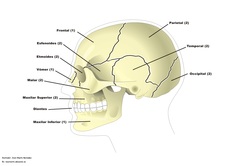

Los huesos del cráneo